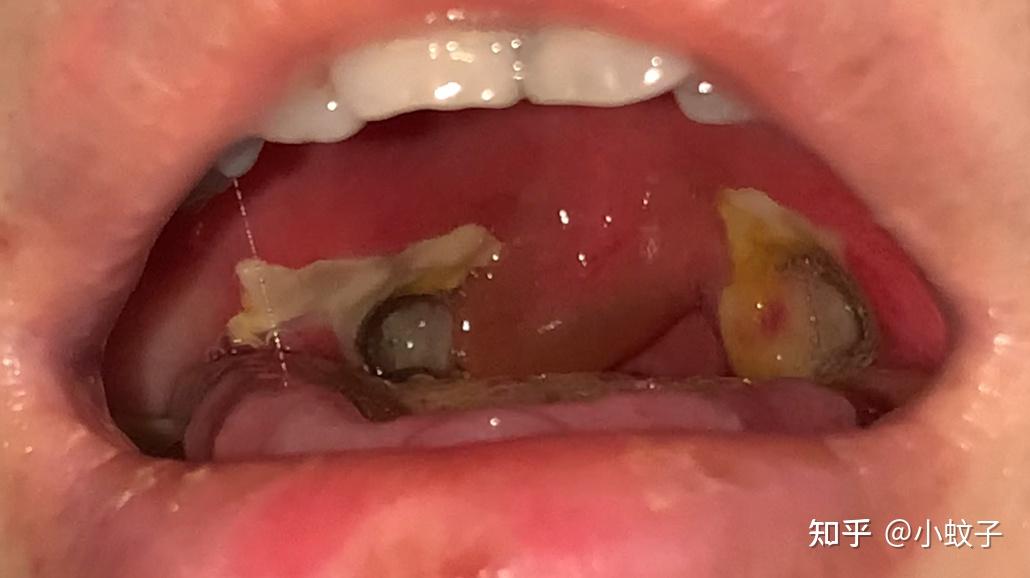

咽部疼痛吞咽困难2天咽部伪膜见图

出院真的是噩梦的开始,因为扁桃体的伤口开始长膜,会出血疼痛不适

一个大朋友的扁桃体切除手术过程记录